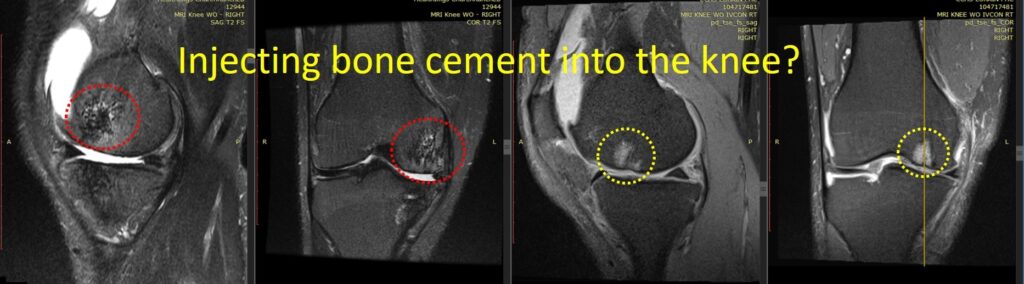

A patient pursued stem cell treatment for knee arthritis after complications from a prior subchondroplasty. During an initial bone cement injection into BMLs, the surgeon, performing the procedure for the first time, unintentionally worsened the condition.

Follow-up MRI images revealed structural changes: the original BMLs (highlighted in yellow dashed circles) appeared as bright spots on imaging, while post-procedure images (red dashed circles) showed areas of bone deterioration, with gaps and holes replacing healthy bone. Over nine months, significant cartilage loss also occurred.

This case underscores that while bone cement can be beneficial when used correctly, improper application can accelerate joint damage rather than provide stabilization. Careful patient selection, proper cement type, and experienced technique are essential for safe and effective subchondroplasty.